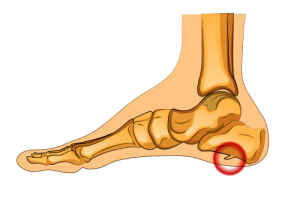

NEUROMA DE MORTON

O que é o Neuroma de Morton?

O neuroma de Morton, também conhecido como neuroma intermetatarsal, é uma condição dolorosa que afeta os nervos que passam entre os ossos metatarsais dos dedos do pé. Geralmente ocorre entre o terceiro e o quarto dedos do pé, embora também possa afetar outros dedos.

Os sintomas do neuroma de Morton geralmente incluem:

Dor aguda, queimação ou formigamento entre os dedos dos pés, geralmente piorando ao caminhar ou ficar em pé por longos períodos.

Sensação de um caroço ou protuberância entre os ossos metatarsais.

Dormência ou sensação de choque nos dedos afetados.